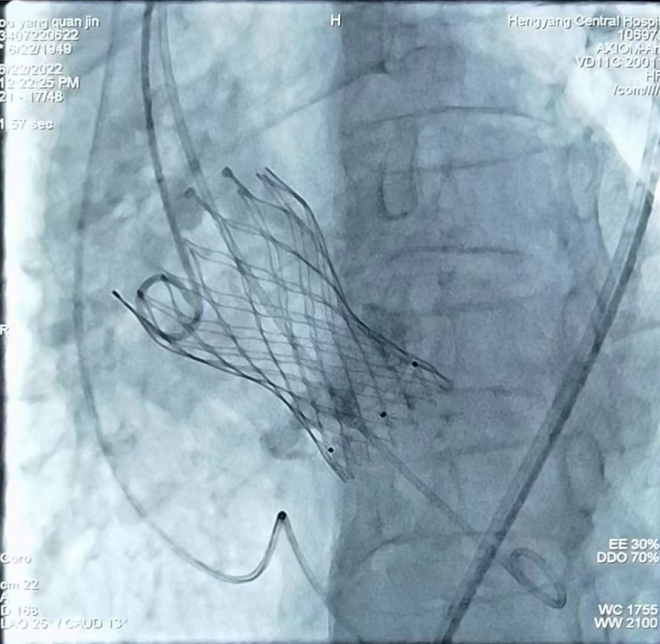

心內(nèi)一區(qū)通訊員何紅丹報道:為推進(jìn)結(jié)構(gòu)心臟病介入這一先進(jìn)技術(shù)的開展,我院組建了以心血管內(nèi)科為主導(dǎo)的TAVR手術(shù)團(tuán)隊,其中包括胸心外科、麻醉科、ICU、手術(shù)室、超聲科專家。6月22日上午,我院在心血管內(nèi)科趙慶禧主任醫(yī)師手術(shù)組及TAVR團(tuán)隊的通力合作下,又成功開展一例TAVR手術(shù),標(biāo)志著我院TAVR團(tuán)隊在技術(shù)積累、流程優(yōu)化和團(tuán)隊建設(shè)取得重大突破,是我院TAVR技術(shù)成熟的一個里程碑。

患者為73歲老年女性患者,心臟彩超示主動脈瓣重度狹窄伴輕中度反流,冠狀動脈CTA示冠狀動脈硬化,主動脈瓣多發(fā)鈣化,右冠狀動脈近、中段管壁鈣化,管腔稍窄。結(jié)合患者年齡大、心功能差,不能耐受開胸?fù)Q瓣等實(shí)際情況,趙慶禧主任組織TAVR團(tuán)隊對患者進(jìn)行了縝密的術(shù)前討論,充分評估了患者主動脈瓣及冠脈的情況,并與患者及家屬進(jìn)行了充分溝通,經(jīng)過反復(fù)研討,制定了一套精密的手術(shù)方案。手術(shù)過程歷時3個小時,患者術(shù)中術(shù)后生命體征平穩(wěn),目前正處于康復(fù)階段。

TAVR手術(shù)即經(jīng)導(dǎo)管主動脈瓣置換手術(shù),是一種通過微創(chuàng)介入導(dǎo)管,將人工心臟瓣膜輸送至主動脈瓣區(qū)域并釋放,完成人工瓣膜置入,治療主動脈瓣狹窄的手術(shù)。TAVR手術(shù)具有創(chuàng)傷小、術(shù)后恢復(fù)快等優(yōu)點(diǎn),使得部分以前無法行開胸瓣膜置換的患者成功進(jìn)行瓣膜置換成為可能。隨著我院TAVR手術(shù)團(tuán)隊臨床經(jīng)驗(yàn)的豐富和器械的不斷發(fā)展,TAVR手術(shù)在我院越來越成熟,標(biāo)志著我院的心臟瓣膜置換進(jìn)入微創(chuàng)時代,為更多的老年、高危、復(fù)雜性心臟瓣膜病患者帶來“心”的希望,為衡陽乃至湘南地區(qū)老百姓的健康帶來了福音。